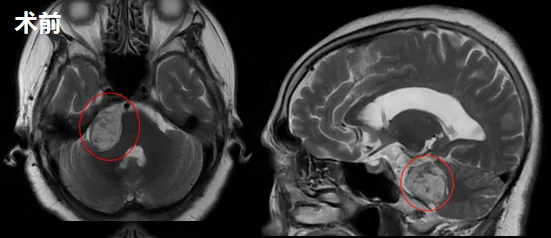

直到2021年末,她的症状急剧加重:右耳听力和耳鸣恶化,右眼视力下降,面部麻木加剧,出现站立不稳。这次的头颅MRI终于揭示了病因——右侧桥小脑角区听神经瘤,最大直径约35mm,已压迫脑干。

肿瘤巨大,手术是唯一出路。但面对“术后面瘫”的高风险,李女士辗转难眠。在查阅大量资料后,李女士联系上巴教授。手术中,巴教授采用个体化入路,结合神经电生理监测和MRI辅助,在显微镜下将肿瘤完整切除,还为李女士保留了大部分秀发。